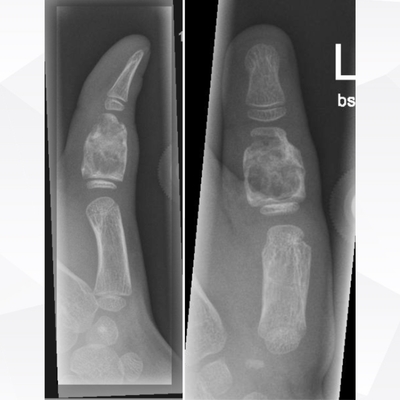

Click on an image below to view more info.